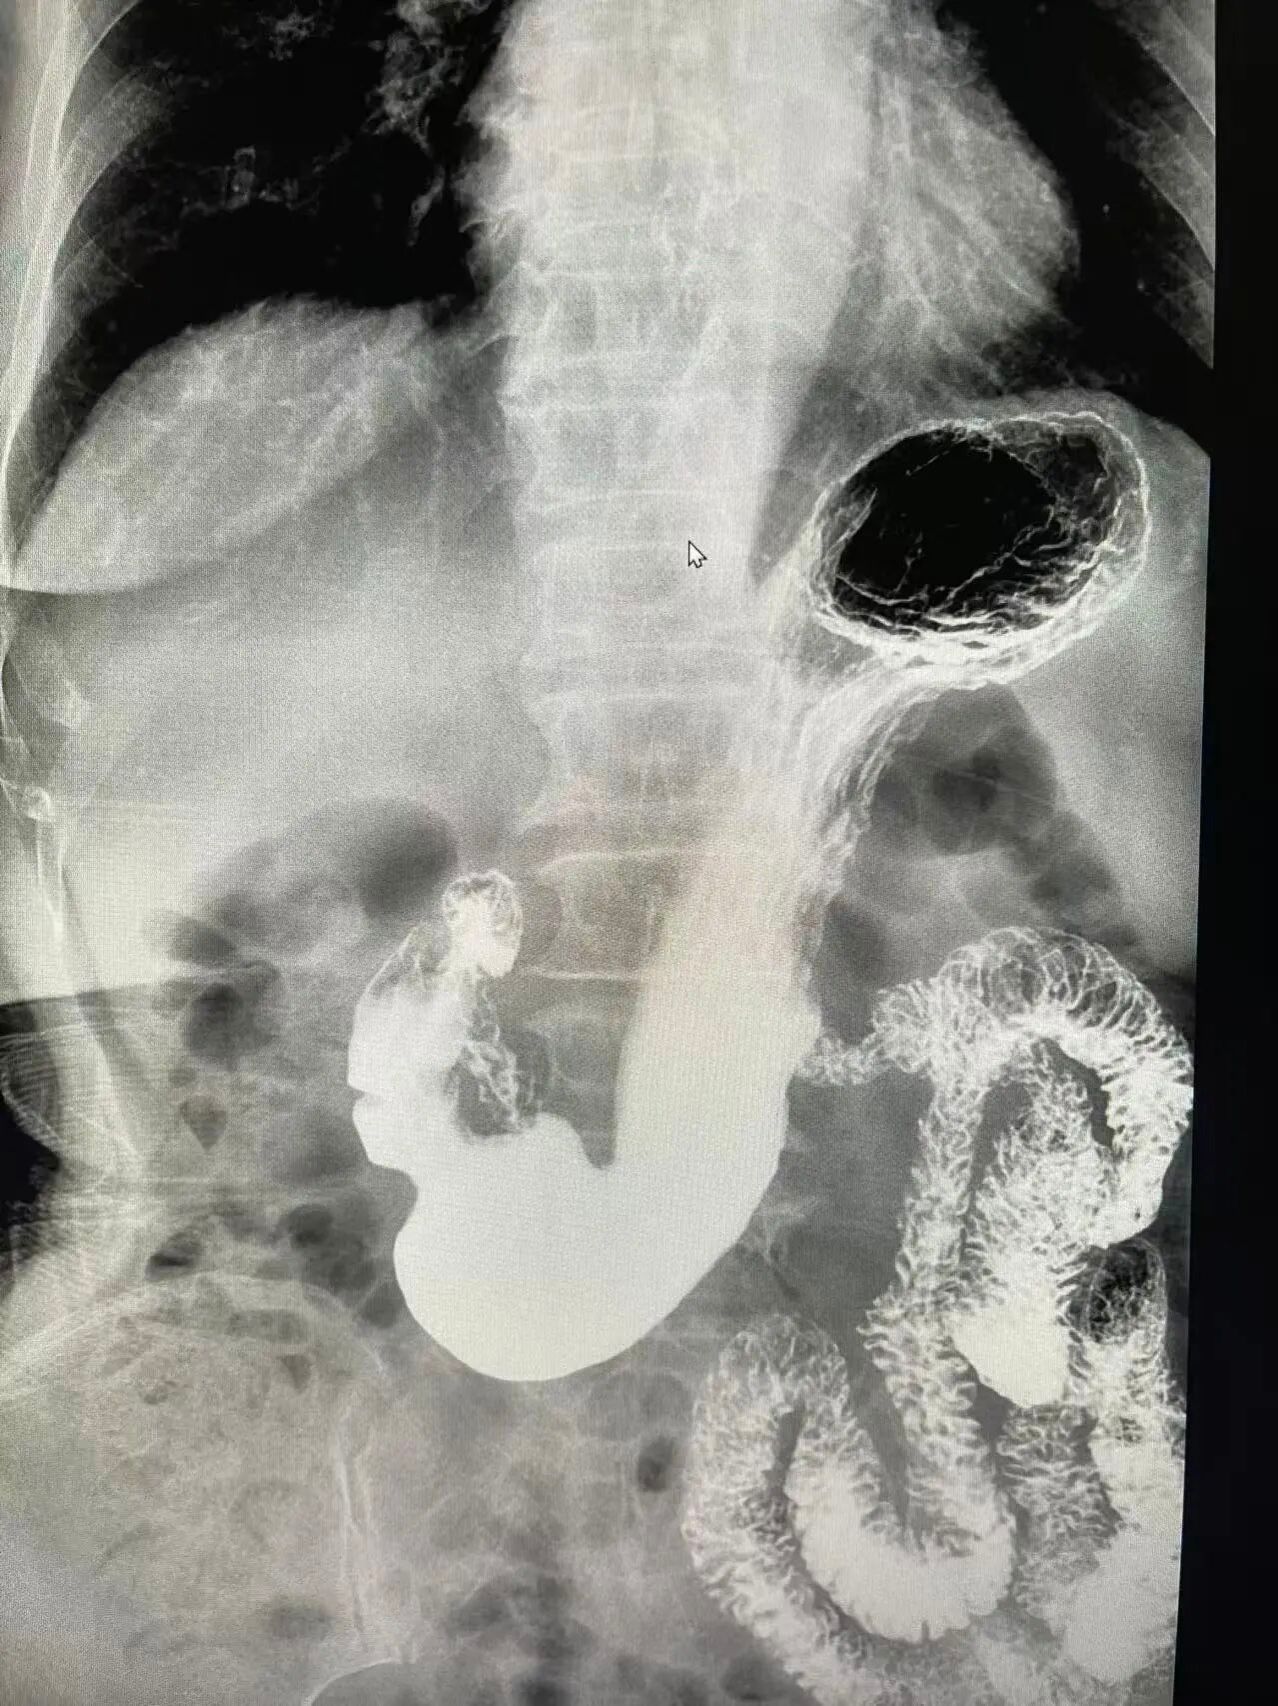

其实,除了胃镜、肠镜,还有一种无痛、无创、舒适、安全的检查方式“消化道钡餐造影”。它不用插管、不用麻醉,喝一杯“白色药水”,在X线透视下,钡剂如同“白色造影剂”均匀涂布在消化道黏膜上,通过多角度、多时相的动态观察,医生不仅能发现微小的黏膜病变,还能实时评估胃肠的蠕动能力和排空功能。

我院引进的数字化胃肠机,结合传统的钡餐造影技术,能够动态、清晰地观察消化道器质性病变和功能性改变,尤其对于胃溃疡、慢性胃炎、十二指肠憩室、消化道肿瘤以及胃下垂等功能性疾病的诊断具有重要临床价值。

可一次性观察食管、胃、十二指肠、空肠、回肠等全段消化道,弥补了胃镜只能看胃和十二指肠上段的局限。

③功能+形态双检查